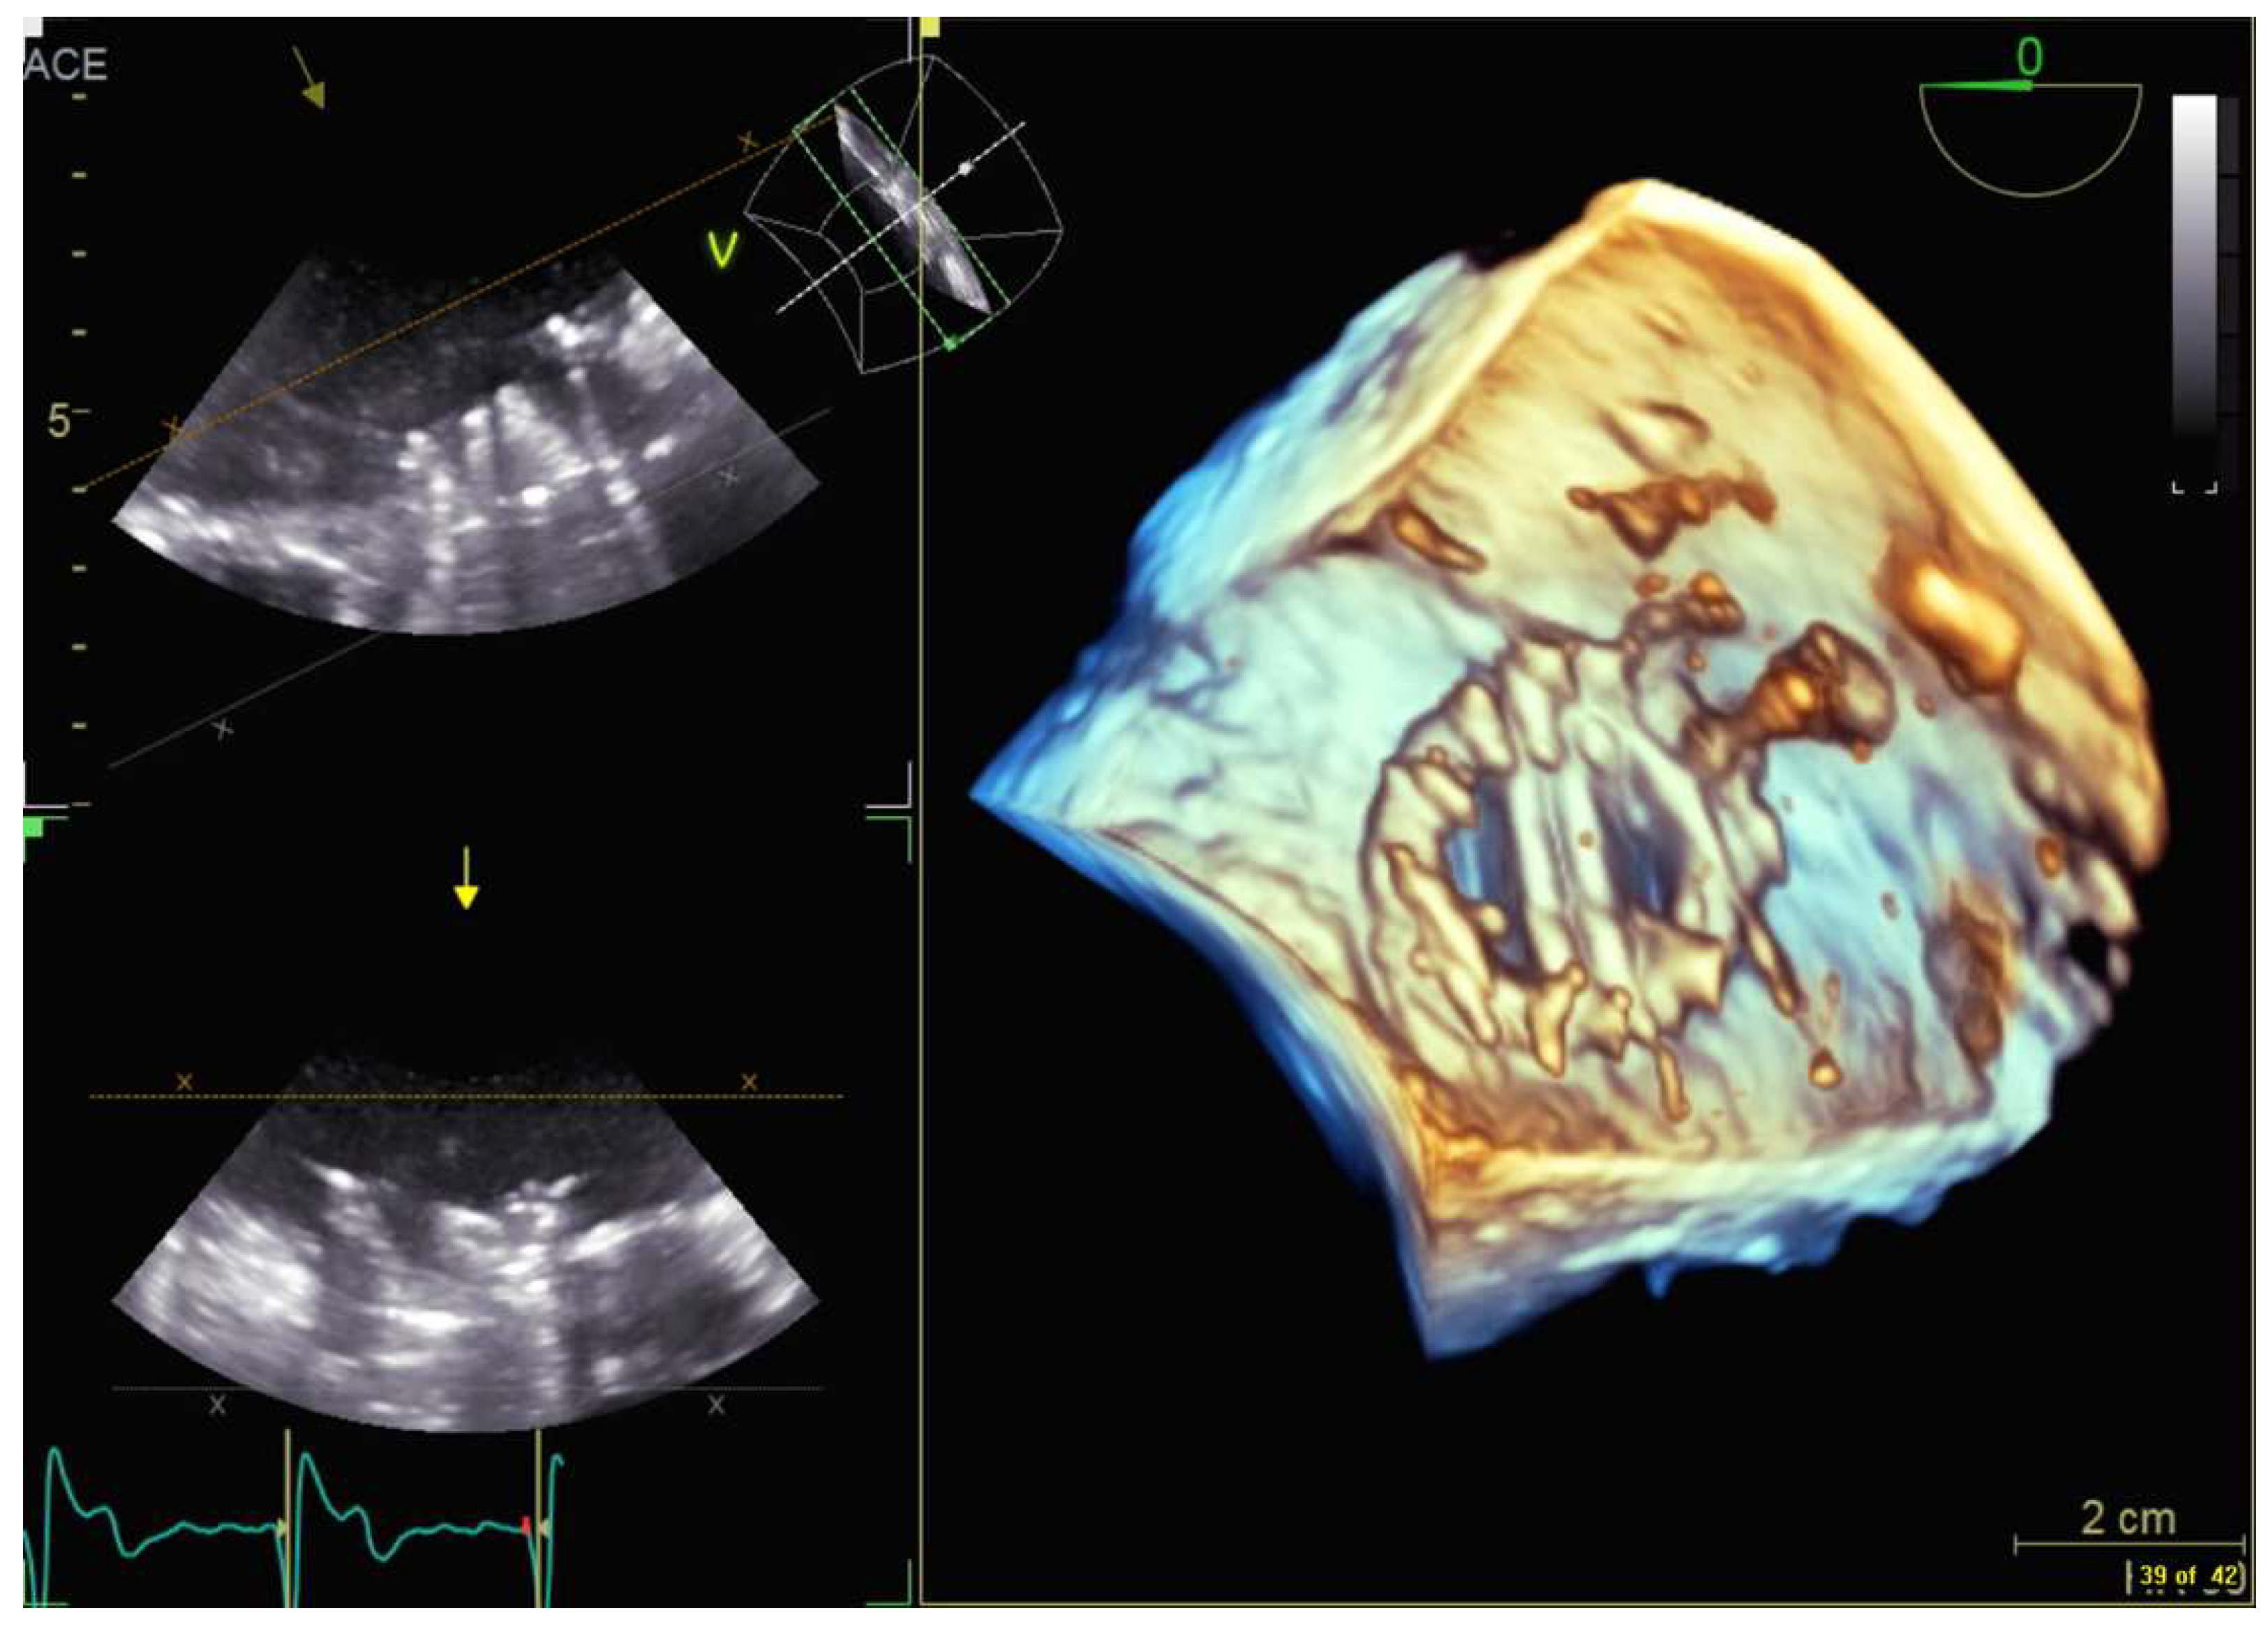

4.2.3. Mitral Valve Repair

4.2.4. Atrial Septal Defect Occlusion